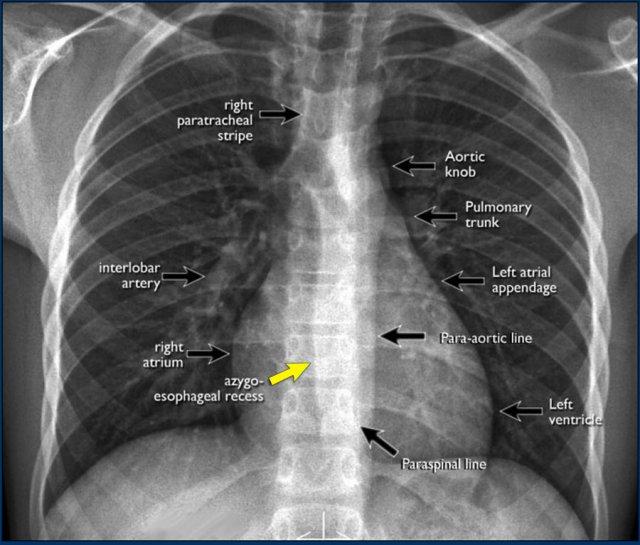

Trên phim X-quang ngực tư thế PA, cần đánh giá cẩn thận tất cả các ranh giới giữa phổi và các cấu trúc lân cận — chẳng hạn như cơ hoành, tim và trung thất.

Tại các ranh giới này, các mặt tiếp giáp giữa phổi và mô mềm tạo thành các hình ảnh có thể nhìn thấy được:

- Các đường hoặc dải (ví dụ: dải cạnh khí quản phải)

- Các bóng mờ viền (ví dụ: cung động mạch chủ hoặc bờ thất trái)

Các đường và bóng mờ viền này đóng vai trò là các mốc giải phẫu và giúp xác định vị trí tổn thương. Khi các đường viền này bị dịch chuyển hoặc bị xóa mờ kèm mất bóng mờ viền bình thường, dấu hiệu bóng mờ viền được xác lập — đây là một đặc điểm chẩn đoán quan trọng.

- Đường cạnh cột sống có thể bị dịch chuyển do áp xe cạnh đốt sống, gãy đốt sống kèm xuất huyết, hoặc u tân sinh lan rộng ra ngoài đốt sống.

- Dày dải cạnh khí quản phải (>2–3 mm) có thể gợi ý hạch to, dày màng phổi, xuất huyết, quá tải dịch hoặc suy tim sung huyết.

- Dịch chuyển đường cạnh động mạch chủ có thể liên quan đến giãn dài động mạch chủ, phình, bóc tách hoặc vỡ động mạch chủ.

Một mặt tiếp giáp trung thất–phổi quan trọng cần đánh giá là ngách tĩnh mạch đơn–thực quản (mũi tên vàng).